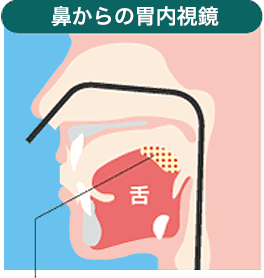

鼻から胃カメラの特長

- 話せる

- 医師と同じ画像を見ながらリアルタイムで話せる。

- 嘔吐感が起きにくい

- スコープが舌の付け根に触れない。

- 苦痛が少ない

- 直径5.9mmの細くしなやかなスコープ。

- 麻酔事故のリスクが少ない

- 鼻腔への麻酔だから、身体への負担が軽い。

この部分にスコープが触れると、

吐き気を感じます。

この部分にスコープは

触れにくい。

また、 患者は医師と会話することができるため、モニターを見ながら医師に質問できるなど安心した診療を受けることができます。